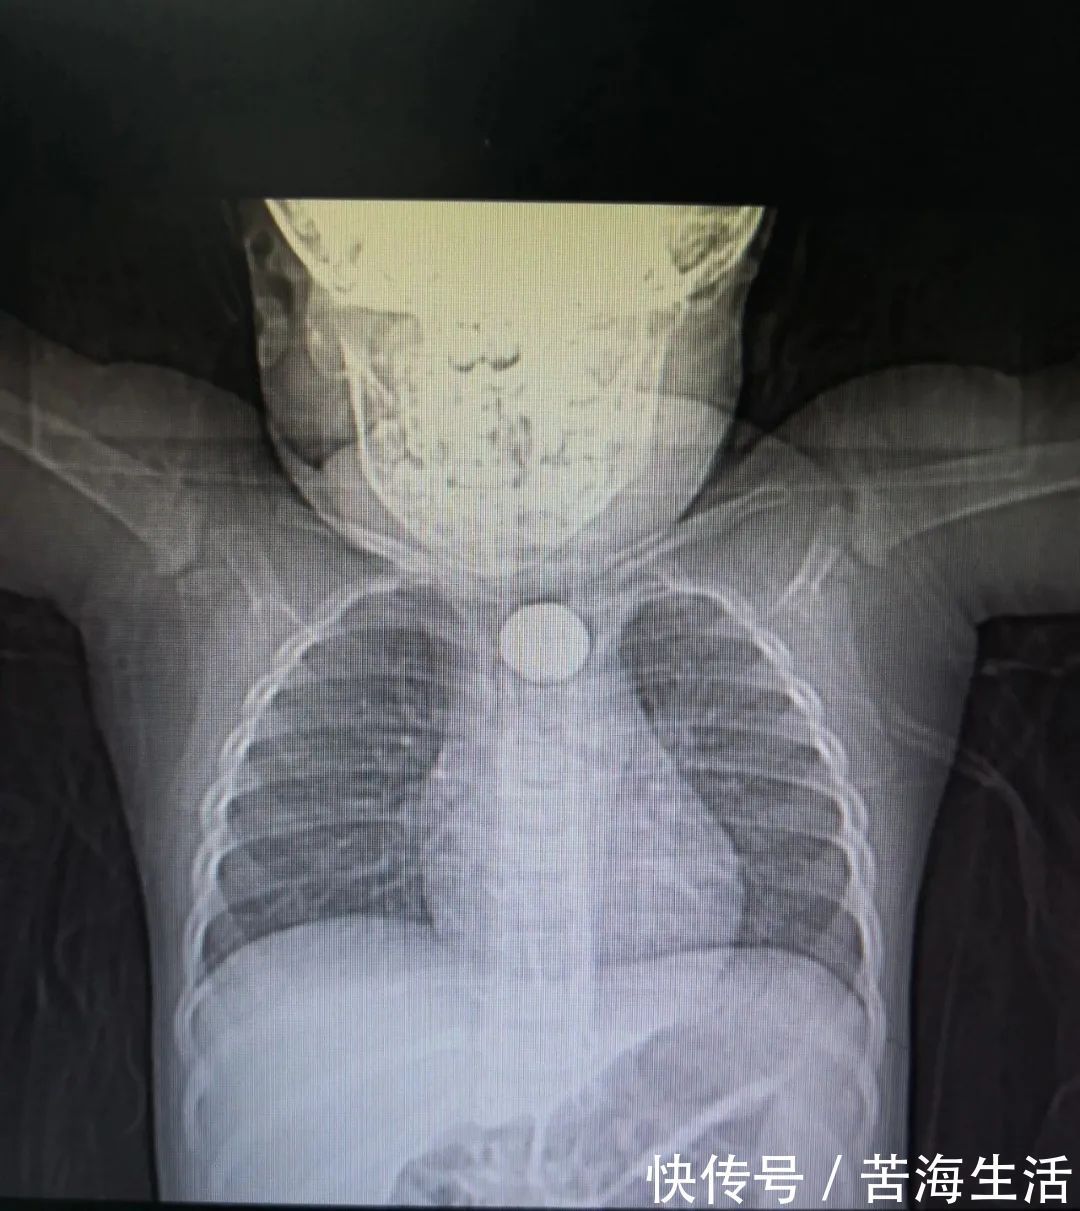

医生看了X光片后发现

孩子吞下的并非硬币

可能是家里常见的纽扣电池!

进一步检查确认,卡在孩子上纵膈与脊柱重叠投影区(胸2-3椎体水平)的“圆形物体”,就是纽扣电池!